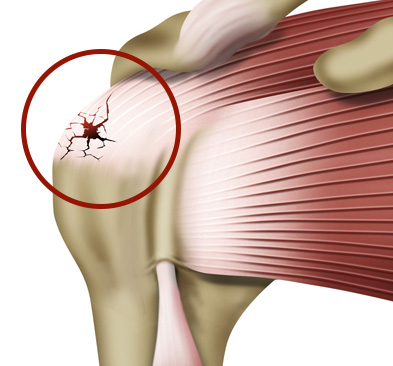

회전근개파열은 파열정도에 따라서 치료법이 달라집니다.

파열의 정도가 미세한 경우라면 비수술적 치료인 약물치료, 주사치료, 체외충격파 등으로

증상이 호전되는 것을 기대할 수 있습니다.

회전근개 파열의 원인은 여러 가지가 있으나

반복적인 움직임이나 과도한 사용으로 인해 근육에 스트레스가 가해지거나, 염증이나 건염 등의 원인으로 힘줄이 약해지면 파열의 위험이 생깁니다.